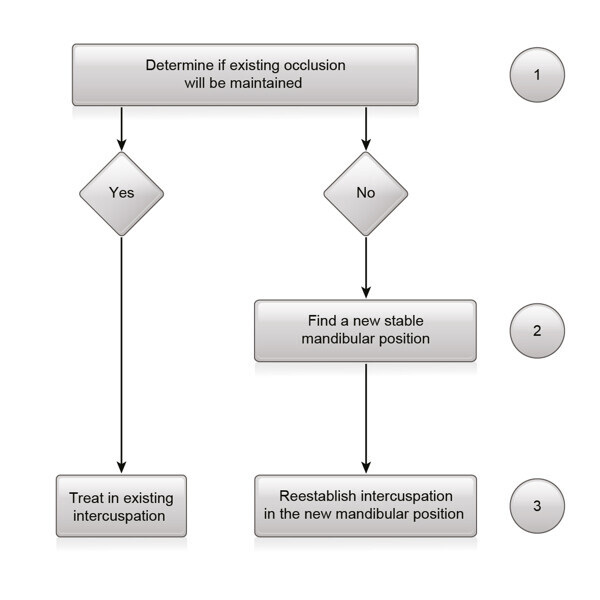

Fig. 11: Clinical decision guideline for occlusal evaluation and treatment.